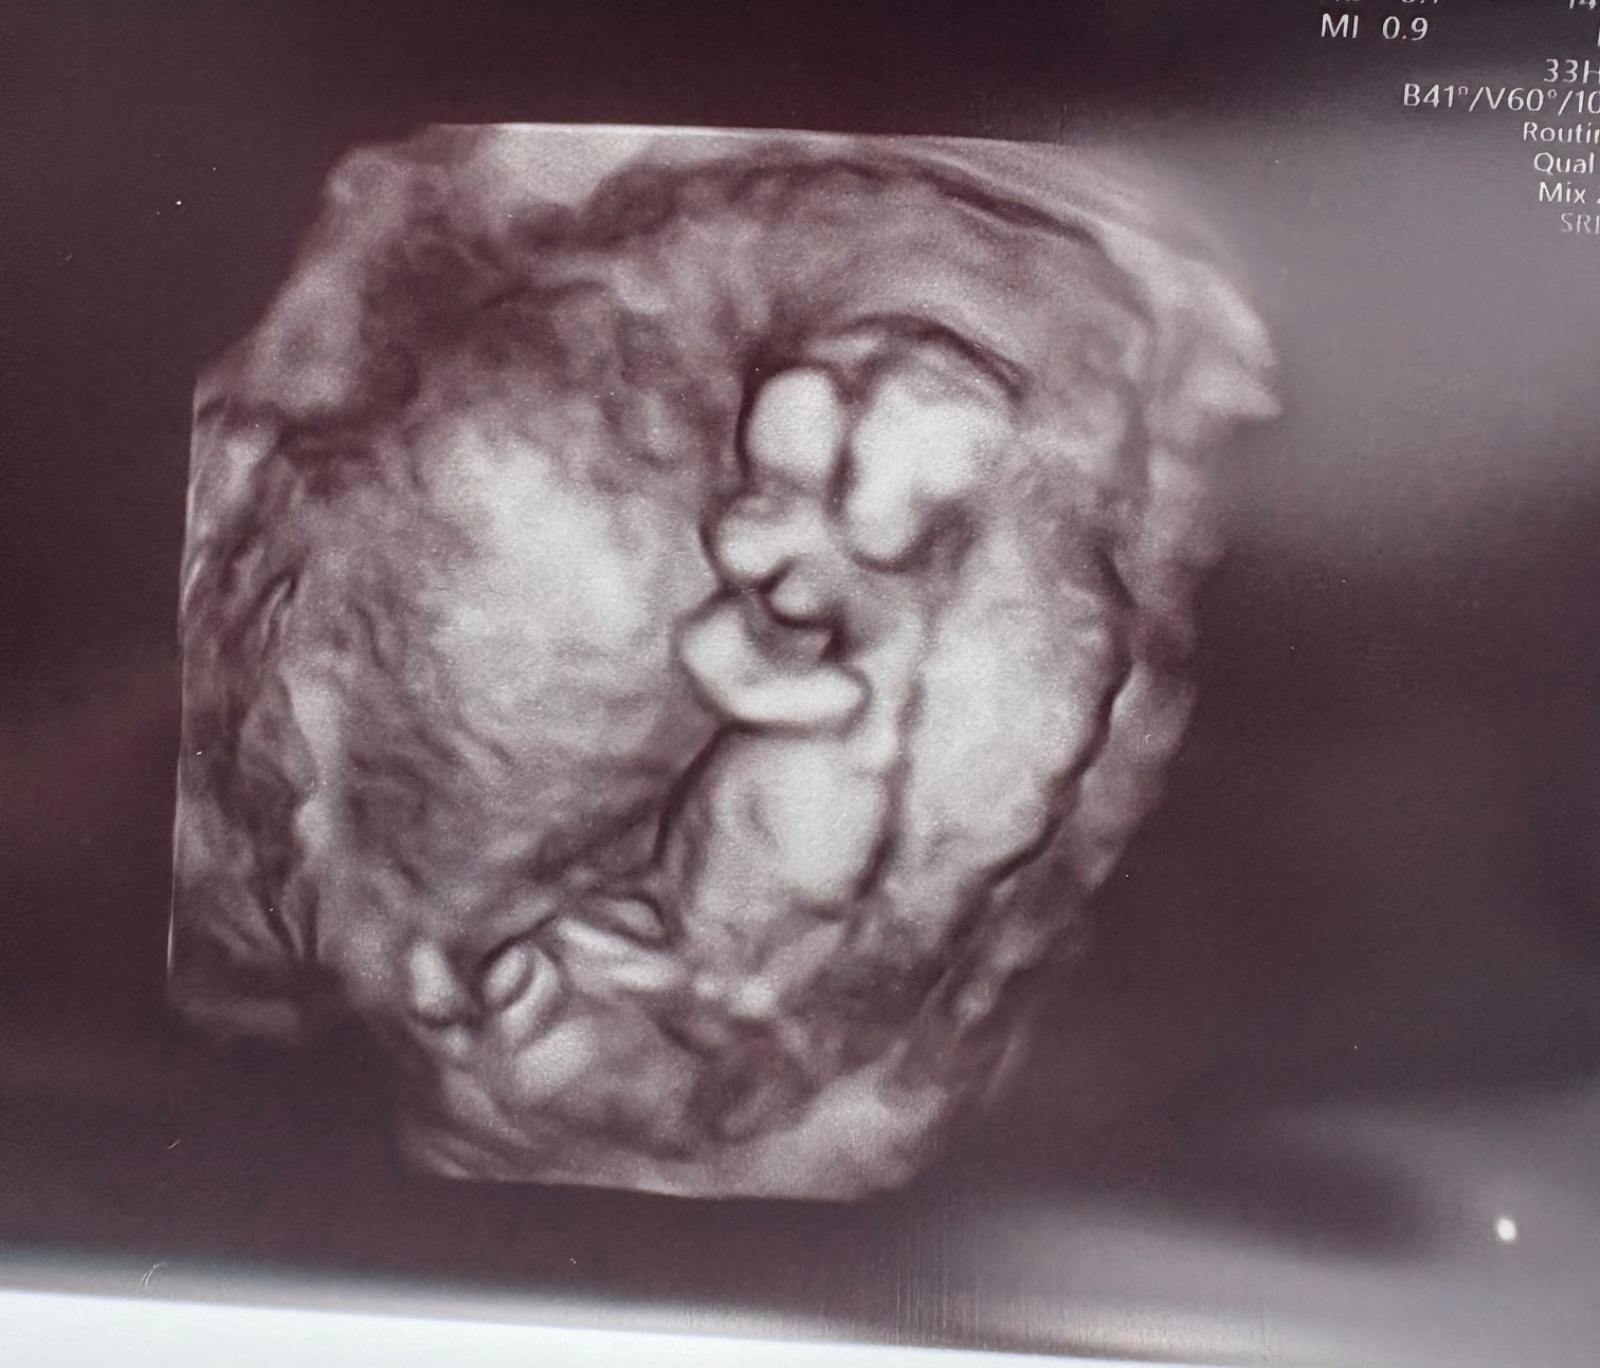

Může foto prvního screeningu odhalit pohlaví miminka?

@berenika39 bohužel ne, lékař řekl, že si je jistý na 70% a že je to málo a že to říkat nebude..:-/ ze musíme počkat, tak sem to jen zde zkusila, kdyby náhodou někdo dokázal odhadnout 🙂

@tessss97 nerekne ti nikdo, jelikoz z fotky opravdu nic poznat nejde. Lekar, je odbornik a pokud on nevidi, tu to neuvidi urcite nikdo. Je to brzo. Vydrz, casu mas jeste spoustu.

@tessss97 nemáš obyčejnou fotku z boku? Z téhle 3D to není poznat.